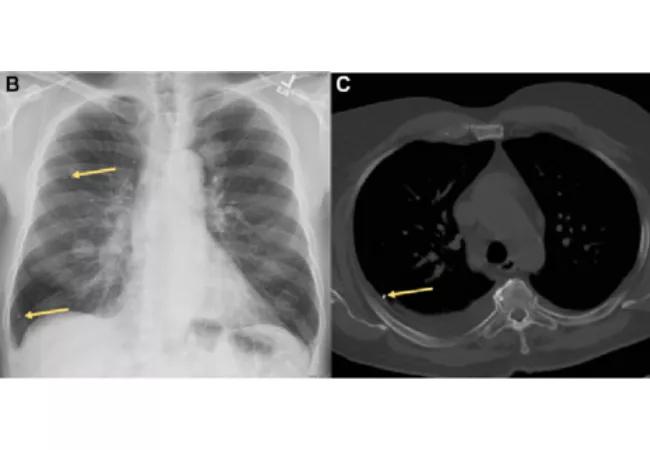

Note the multiple tiny embolized brachytherapy seeds in the right lung (arrows) on this postero-anterior chest radiograph (B), as well as the metallic density indicating an embolized brachytherapy seed in the right upper lobe on the axial CT at the level of the aortic arch (C).